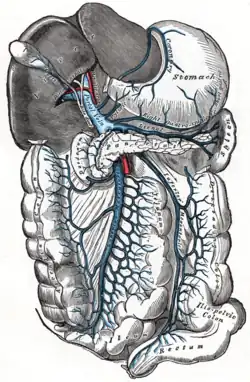

The portal vein (in light blue) and its tributaries. It is formed by the superior mesenteric vein, inferior mesenteric vein, and splenic vein. Lienal vein is an old term for splenic vein. | |

The portal vein is usually formed by the confluence of the superior mesenteric, splenic veins, inferior mesenteric, left, right gastric veins and the pancreatic vein.

In most individuals, the portal vein is formed by the union of the superior mesenteric vein and the splenic vein.[5] For this reason, the portal vein is occasionally called the splenic-mesenteric confluence.[4] Occasionally, the portal vein also directly communicates with the inferior mesenteric vein, although this is highly variable. Other tributaries of the portal vein include the cystic and the left and right gastric veins.[6] and also pararumbilical vein and prepyloric vein.